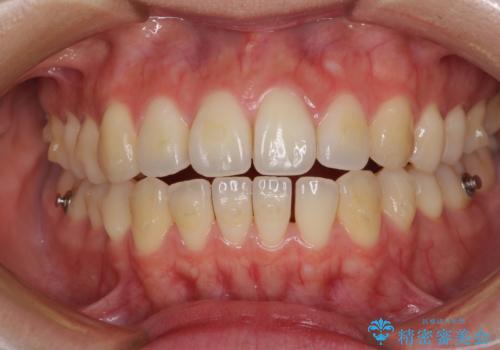

オープンバイトでかみにくい インビザラインによる矯正治療

- インビザライン

- 11ヶ月

上下の奥歯を圧下させるようにすることで、前歯を接触させるように計画しました。

上下の隙間に舌が入り込むことがオープンバイトの原因であったため、舌の筋肉のトレーニングも並行して行い、後戻りの抑制を図りました。